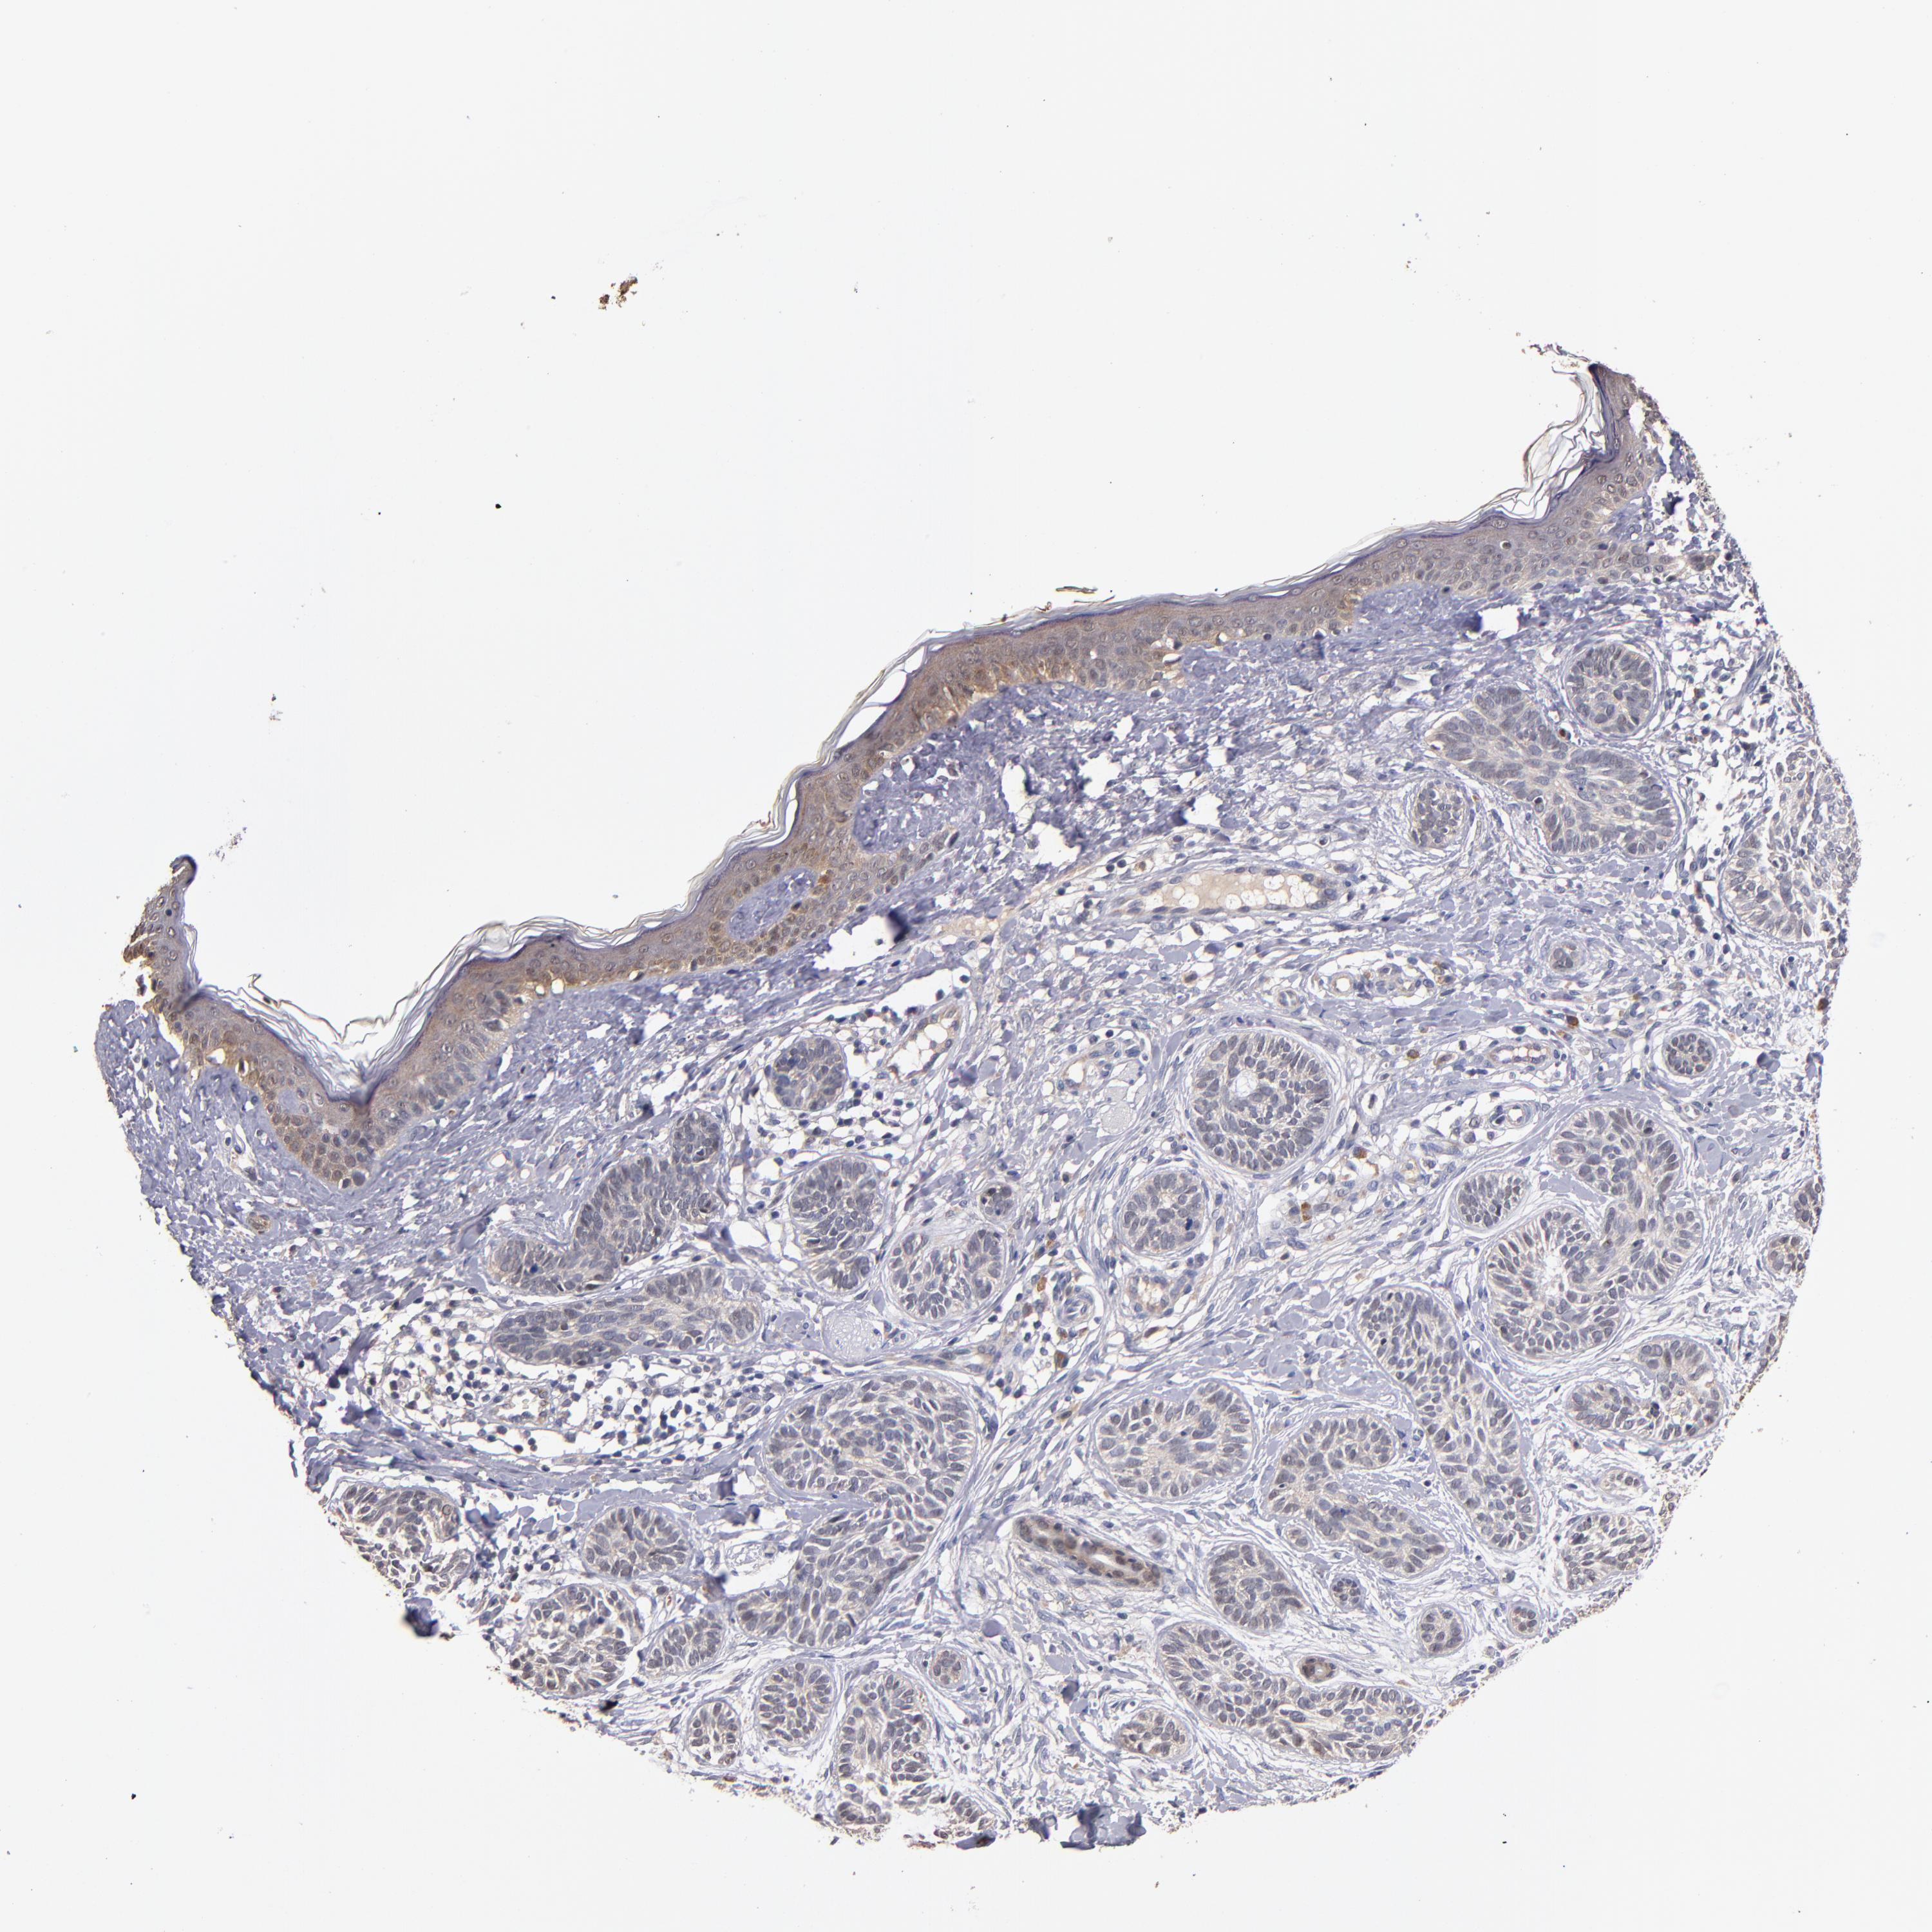

Basal cell and squamous cell cancer

SKIN CANCER - Protein expressioni

A mouse-over function shows sample information and annotation data. Click on an image to view it in a full screen mode. Samples can be filtered based on level of antibody staining by selecting one or several of the following categories: high, medium, low and not detected. The assay and annotation is described here.

Antibody stainingi

Antibody staining in the annotated cell types in the current human tissue is reported as not detected, low, medium, or high, based on conventional immunohistochemistry profiling in selected tissues. This score is based on the combination of the staining intensity and fraction of stained cells.

Each image is clickable and will lead to virtual microscopy that enables deeper exploration of all samples and also displays staining intensity scores, fraction scores and subcellular localization as well as patient and tissue information for each sample.

Antibody HPA003054

Squamous cell carcinoma, NOS